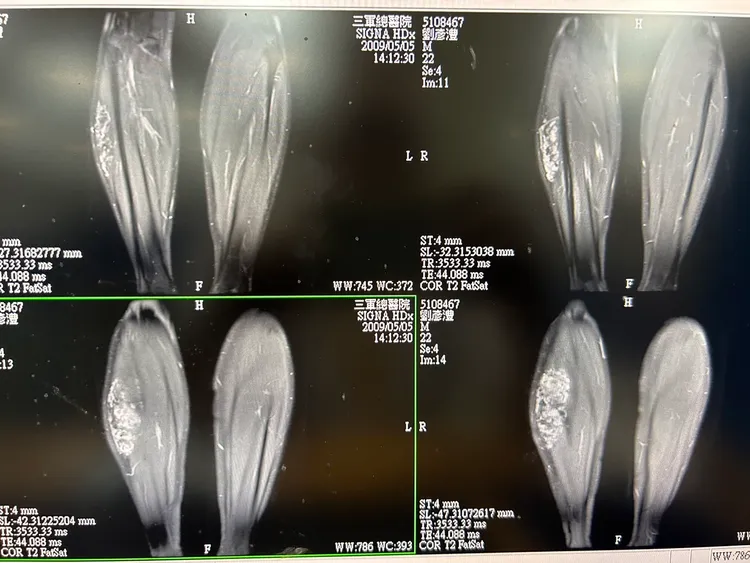

劉彥澧公布三總診斷證明書。劉彥澧提供

劉彥澧出示三軍總醫院的診斷證明(2009年1月)表示,醫師當時診斷他右小腿有動靜脈血管瘤,無法做久站、奔跑、游泳等正常運動,同年8月在高雄榮總的複檢,是他自行前往,醫師同樣判定為動靜脈瘤,造成運動功能障礙,屏東縣政府當年度據此判定為免役體位。

劉彥澧指出,相對於溫朗東不負責任的指控,他負責任地公布個人病歷,2009年與上周的核磁共振造影都清楚顯示,小腿血管瘤至今還在,大小為長13.4公分、寬9.1公分及厚度2.7公分,醫生也說無法以外科手術摘除,否則會走路困難。